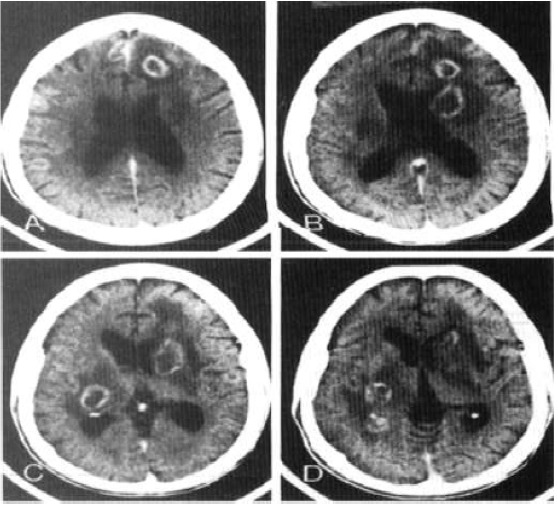

Sr. FS, 39 anos, convive com HIV há 10 anos, faz uso irregular de terapia antirretroviral e não sabe referir seu último CD4 dosado. Ele procura atendimento no pronto-socorro por quadro de rebaixamento do nível de consciência há três dias, associado à intensa cefaleia. Apresentou três episódios de convulsões tônico-clônicas generalizadas. O exame neurológico simplificado demonstrou hemiparesia à esquerda, Glasgow 13, sem sinais de irritação meníngea e com fundo de olho normal. Foi realizada tomografia, de acordo com a imagem a seguir:

Considere que a principal hipótese diagnóstica foi confirmada. Qual deve ser a conduta CORRETA?